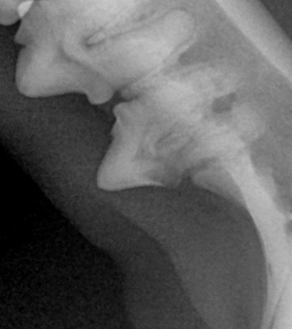

BEFORE

AFTER